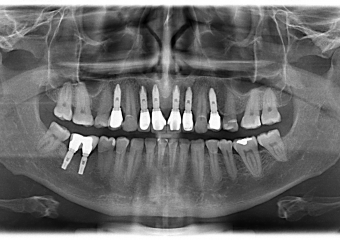

Imagem com próteses fixas individuais em porcelana instaladas

Raio X final